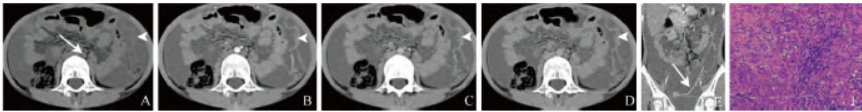

CT平扫示:腹膜广泛斑片状、不规则结节状增厚,增强扫描呈不均匀强化,腹腔大量液体密度影,肠系膜根部多发肿大淋巴结,可见多发侧支血管(图1A~E)。手术及病理:经腹腔镜探查示肠系膜、大网膜充血、水肿,未见肿大淋巴结,腹壁未见肿物,患者大网膜呈串珠样变,盆腔大网膜粘连腹腔。

病理镜下肿瘤细胞呈嗜伊红色多边形,细胞有轻度异型性、泡状核、核仁明显,少见核分裂象,并呈不规则腺管样、实性巢团、乳头状排列,间质炎细胞浸润、淋巴组织增生(图1F)。病理诊断:恶性腹膜间皮瘤(malignant peritoneal mesothelioma,MPM)。

图1 女,9岁,MPM。CT平扫示广泛腹膜斑片状、不规则结节状增厚(箭头),腹腔大量液体密度影,肠系膜根部多发肿大淋巴结(箭,A);增强扫描动脉期、门静脉期和延迟期,增厚腹膜明显强化(箭头,B~D);增强扫描动脉期冠状位见多发侧支血管(箭,E);病理镜下肿瘤细胞呈嗜伊红色多边形,细胞有轻度异型性、泡状核、核仁明显,少见核分裂象,并呈不规则腺管样、实性巢团、乳头状排列,间质炎细胞浸润、淋巴组织增生(HE,×200,F)